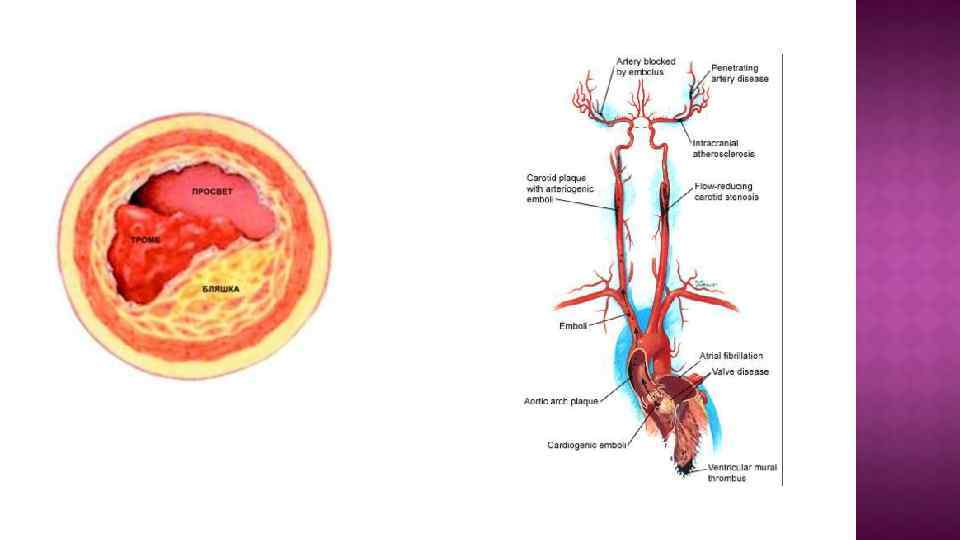

Этиология ТИА 1. Кардиогенная эмболия. Источники высокого риска эмболии мозговых сосудов: искусственный клапан сердца, итральный стеноз + фибрилляция предсердий, постоянная форма фибрилляции предсердий, тромб левого предсердия, тромб левого желудочка. Синдром слабости синусового узла. Острый период инфаркта миокарда(до 4 недель). Дилятационная кардиомиопатия. Акинезия левого желудочка. Миксома предсердия. Инфекционный эндокардит. 2. Атеросклероз сонной, позвоночной артерий и крупных ветвей бассейна этих артерий. Артерио-артериальная эмболия. Симптомный каротидный стеноз (более 50% просвета артерии), гемодинамически значимый.

Этиология ТИА 1. Кардиогенная эмболия. Источники высокого риска эмболии мозговых сосудов: искусственный клапан сердца, итральный стеноз + фибрилляция предсердий, постоянная форма фибрилляции предсердий, тромб левого предсердия, тромб левого желудочка. Синдром слабости синусового узла. Острый период инфаркта миокарда(до 4 недель). Дилятационная кардиомиопатия. Акинезия левого желудочка. Миксома предсердия. Инфекционный эндокардит. 2. Атеросклероз сонной, позвоночной артерий и крупных ветвей бассейна этих артерий. Артерио-артериальная эмболия. Симптомный каротидный стеноз (более 50% просвета артерии), гемодинамически значимый.

Патогенез. Механизмы ТИА: 1. Атеротромботический атеросклеротическая бляшка → тромб → сужению просвета артерии+ отрыв тромба → артерио-артериальная эмболия церебральных сосудов. 2. Кардиоэмболический тромб в полостях и клапанном аппарате сердца →эмболия церебральных сосудов. 3. Гемодинамический падение системного АД + симптомный гемодинамически значимы стеноз (более 50% просвета) крупных экстра- и интрацеребральных артерий → гипоперфузия.

Патогенез. Механизмы ТИА: 1. Атеротромботический атеросклеротическая бляшка → тромб → сужению просвета артерии+ отрыв тромба → артерио-артериальная эмболия церебральных сосудов. 2. Кардиоэмболический тромб в полостях и клапанном аппарате сердца →эмболия церебральных сосудов. 3. Гемодинамический падение системного АД + симптомный гемодинамически значимы стеноз (более 50% просвета) крупных экстра- и интрацеребральных артерий → гипоперфузия.